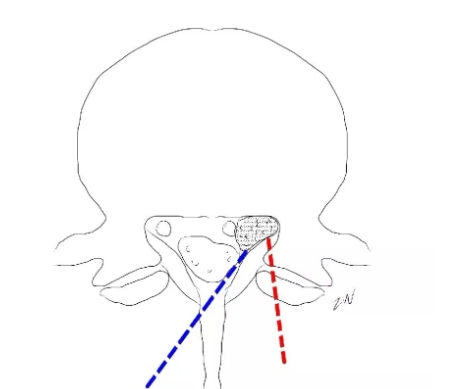

UBE经对侧椎板下入路治疗远端脱垂型腰椎间盘突出症!